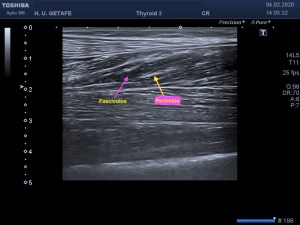

La radiografía revela aumento de las partes y se refrenda en la ecografía como puedes ver en la imagen aunque aún no hay afectación en el hueso en el caso que te presento hoy.

Ecografícamente y debido a su levedad, en el caso de hoy solo observamos cambios en las partes blandas de la cara lateral de la cabeza del quinto metatarsiano, este tejido se muestra heterogéneo, la cortical del hueso ligeramente prominente sin afectación de la misma.